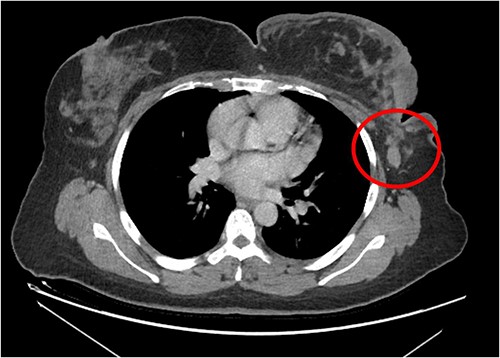

The patient was referred to medical oncology clinic. On exam, she had an eastern cooperative oncology group-performance status of zero, was in pain from her left breast. Assessment of the breast lump revealed a palpable, huge left breast mass, hard in consistency, around 10 cm in largest diameter. There were no palpable lymph nodes in the left axilla. Examination of the right breast was unremarkable. The affected breast is shown in Fig. 1. Otherwise, her chest and abdomen exam were unremarkable, with no lower limb edema. Baseline chest-abdomen–pelvis computed tomography (CT), shown in Fig. 2, showed a large left breast mass 8.0× 2.0 × 4.7 cm with diffuse skin thickening, few axillary lymph adenopathy, the largest of which measured 1.9 cm (shown in Fig. 3), with no distant metastasis. No magnetic resonance imaging was obtained prior to treatment as it was unavailable at the institute. The case was discussed by a multidisciplinary team of medical oncologists, radiation oncologists, surgical oncologists and pathologists. The final decision was that the patient should be treated as a case of high-grade sarcoma, so she was started on ifosfamide–adriamycin (IA) protocol (ifosfamide, 2500 mg/m2, mesna, 800 mg/m2 and doxorubicine, 75 mg/m2 intravenous (IV) for 3 days) as neoadjuvant, to be followed by surgery and adjuvant radiotherapy and chemotherapy. Paraffin blocks were requested by the pathologists for case revision at our institute.

Left breast mass along with involved axillary lymph nodes, encircled.